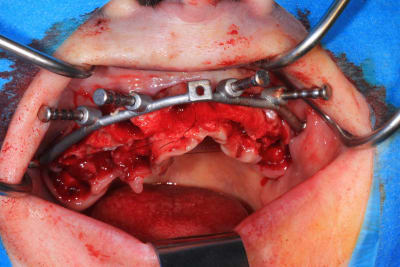

Le cas N°2 en images reelles :)

Guide métal avec support clavette, os assez fin : il est prévu un sticky bone complet : donc : lambeau avant extraction, positionnement du guide base et forage des clavettes, positionnement du guide implant, pose des piliers MU, controle des axes prothétique avec le guide pilier, collage des piliers prov sur le bridge a armature métal, occlusion nickel, sticky bone et PRF, sutures suspendues.

Voilà les photos du cas , avec un peu de retard.